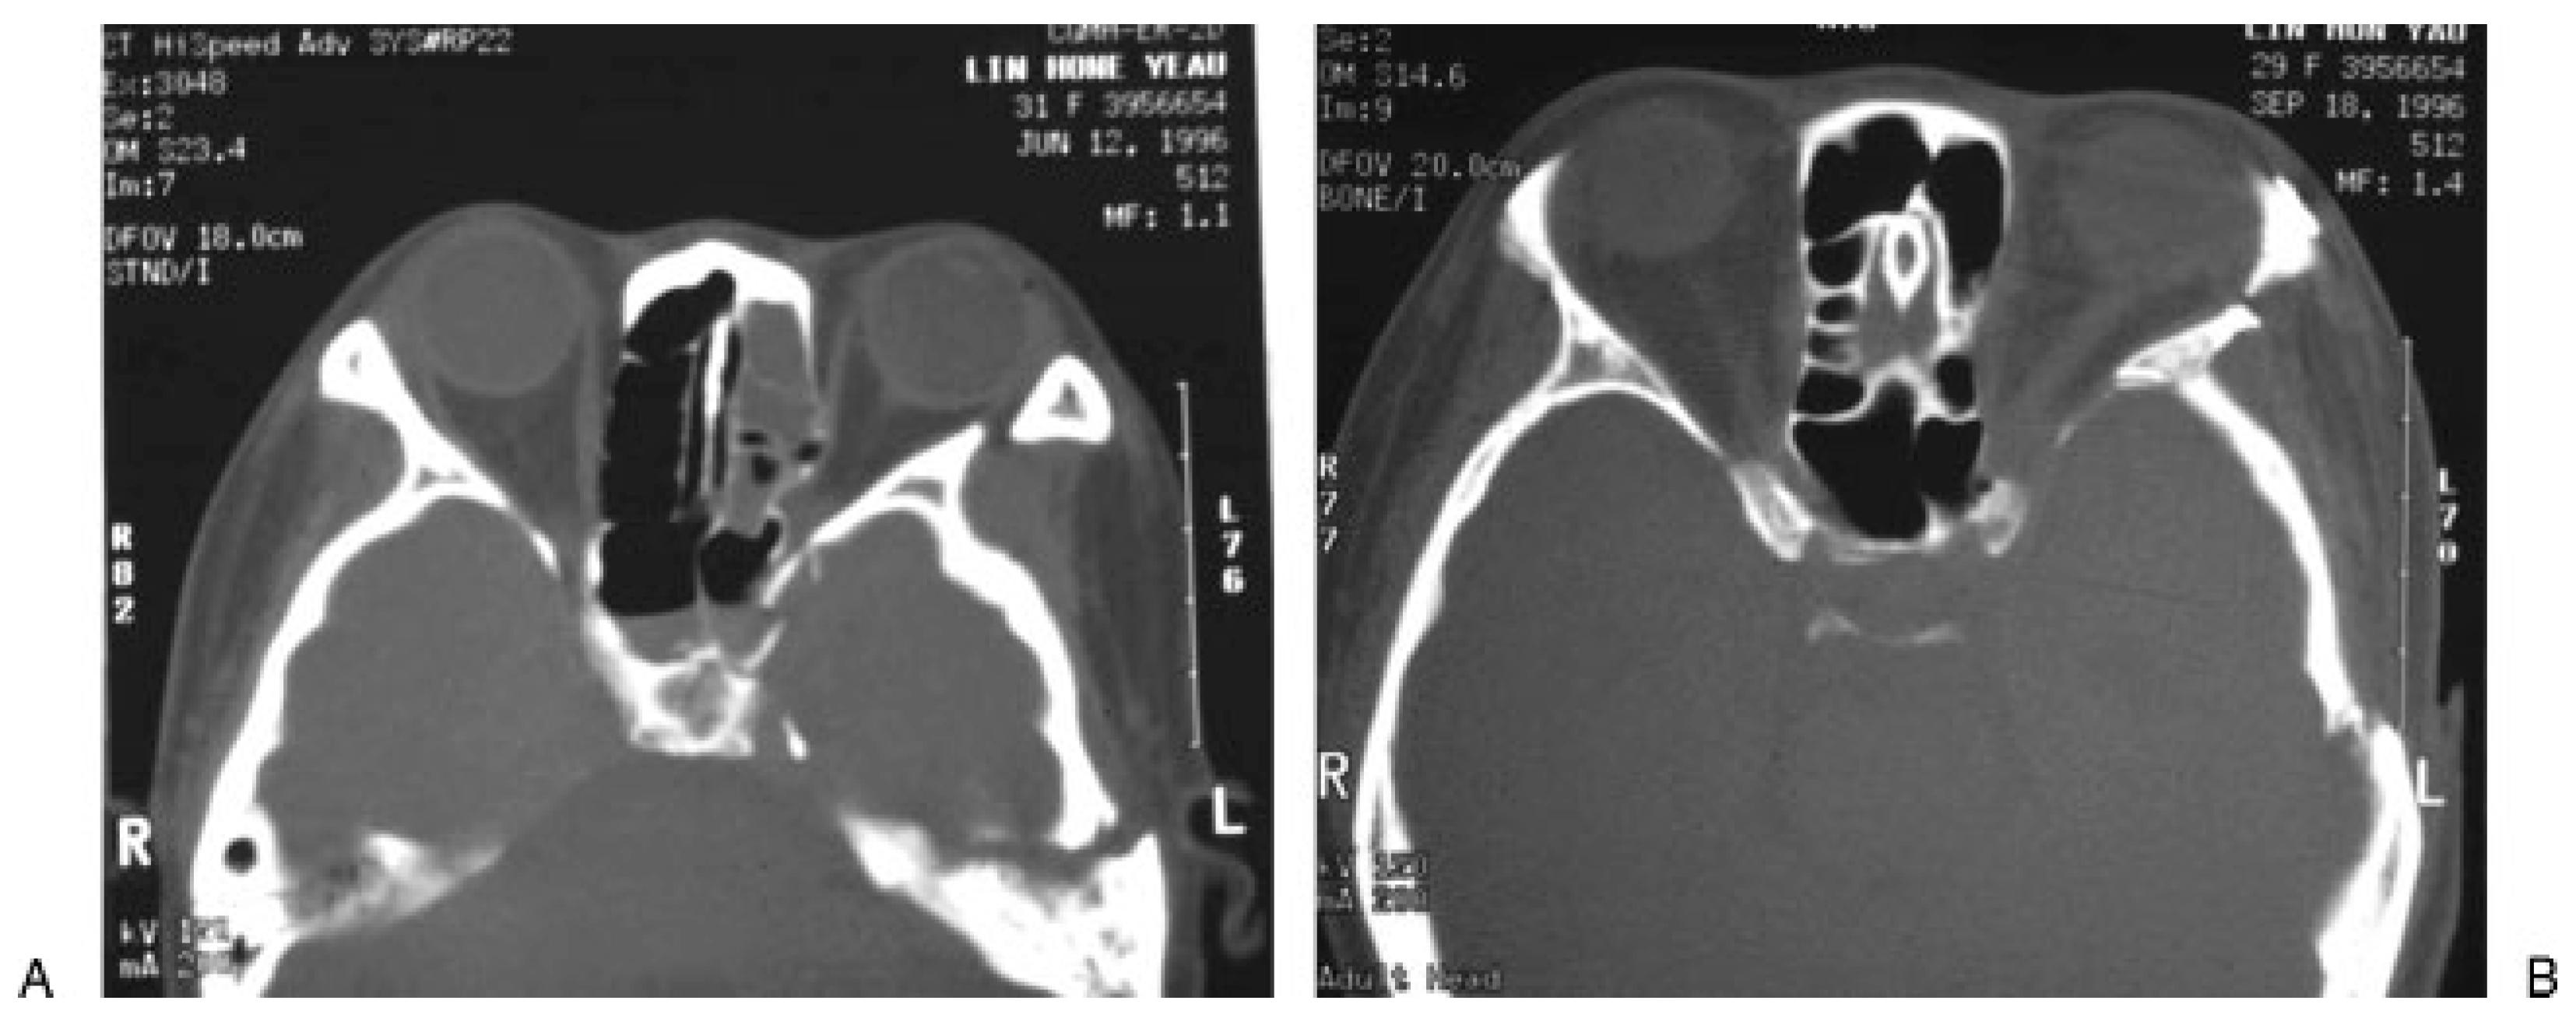

Surgical intervention may be indicated in the presence of significant narrowing of the SOF from the displaced fracture fragment [28]. Murakami [36] described four different routes for decompression of the SOFS: (1) the extranasal intraorbital route, for decompression of the lateral wall of the SOF, (2) the modified extranasal intraorbital route with protection of the trochlear nerve, (3) the extranasal transethmoidal route to decompress the medial wall of the SOF, and (4) the transtemporal route, which is indicated in case of fulminating suppu- ration around the SOFS. When orbital blow-in fracture fragment causes impingement of orbital contents at the SOF, a combination of intracranial and extracranial approach, described by Antonyshyn et al., is adopted for deep orbital decompression to treat SOFS. They reported that three of four patients with traumatic SOFS resolved completely after surgical intervention [19]. How- ever, this method did not specifically decompress the SOF. The author’s surgical method is direct decom- pression of the SOF. When the patient has an evidence of significant depressed sphenoid fracture with compres- sion at SOF, the coronal incision is used to approach the SOF. The dissection plane of the anterior scalp is at the subgaleal-supraperiosteal level centrally and at the tem- poral region just above the plane of the deep temporal fascia. The periosteum is incised at 2 cm above the supraorbital rim and the subperiosteal dissection pro- ceeds until the supraorbital rim, lateral orbital rim, and the zygomatic arch are exposed. The zygoma osteotomy is performed, which mimics zygomatic fracture. If the concomitant zygomatic fracture exists, the zygomatic fracture segment is elevated laterally along its fracture line followed by temporal craniotomy with the assistance of a neurosurgeon. The globe is gently retracted with a malleable retractor to expose the displaced fracture segment of sphenoid bone near the SOF (Figure 6). The narrow SOF is decompressed by removing the greater wing of the sphenoid bone whereas the temporal lobe is carefully protected. After adequate decompression of SOF is achieved, the bone flap and the zygomatic seg- ment are anatomically placed back and fixed with mini- plates. Following this operation, the movement of the eyeball and sensory function usually recover within 3 to 6 months (Figure 7).

Figure 6.

Intraoperative view of left orbit after a combina- tion of intracranial-extracranial approach. The depressed sphenoid bone is exposed (arrow).

Figure 7.

Example of the depressed left sphenoid and temporal bone fractures causing superior orbital fissure syndrome (SOFF). (A) Preoperative axial view of computed tomographic (CT) scan. (B) Postoperative CT scan demonstrating adequate decompression at the superior orbital fissure.